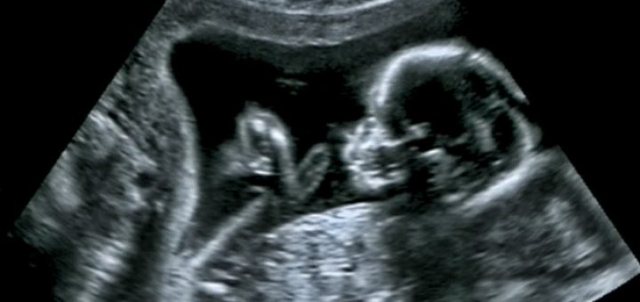

Çdo nënë e re pret me padurim për ditën kur do të shoh për herë të parë në ultratinguj fëmijën e saj. Infermierja tregon pjeset…